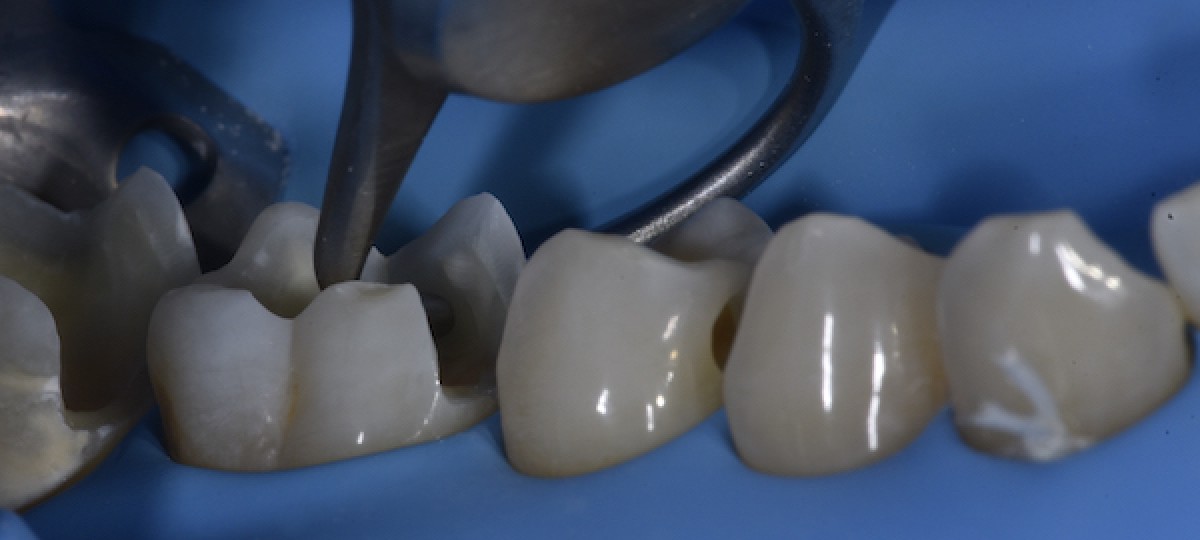

After initial cavity cleaning, it was possible to observe a crack of the mesio-lingual cusp of 4.6. (Fig.3)

The cracked cusp thickness was measured with a caliber. A thickness under 1.5mm was found in the upper third of the cusp, which was not supported by sound dentin (Fig.4)

Impression of the lingual cusps of 4.6 with a rigid silicon material (Fig.5)